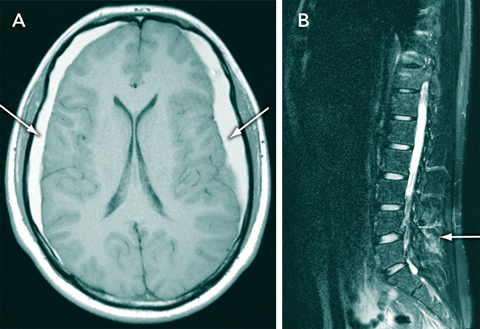

A 16-year-old boy with a 3-month history of intermittent postural headaches presented with sudden worsening headache after a game of soccer. The results of a neurological examination were unremarkable. Magnetic resonance imaging showed elongation of the midbrain, bilateral frontoparietal subdural haematomas (Figure, A), and a collection of fluid within the soft tissues overlying the lumbar spine (Figure, B). The cerebrospinal fluid (CSF) opening pressure on lumbar puncture was low (60 mmHg). Spontaneous intracranial hypotension was diagnosed, and the response to conservative treatment was good.

Intracranial hypotension has characteristic imaging features, which include elongation of the midbrain, linear enhancement of the pachymeninges and subdural effusions.2 Patients are predisposed to subdural haemorrhage after minor trauma as a result of “stretching” of the dural veins. Intracranial hypotension is commonly misdiagnosed as migraine, meningitis or a psychogenic disorder.1 Most cases resolve spontaneously, but intractable headaches may be successfully treated with steroids, epidural blood patches or surgery.1